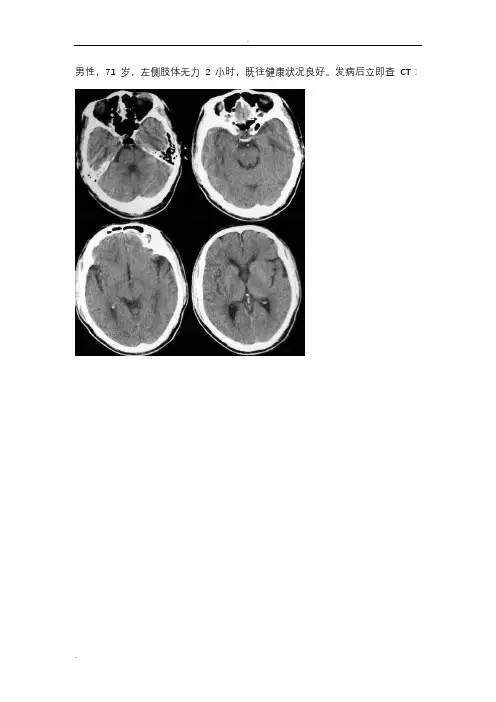

男性,71岁,左侧肢体无力2小时,既往健康状况良好。

发病后立即查CT:从这两张片子看,都没有很明显的病灶,但仔细看可见右侧颞顶叶片状低密度影,脑沟回模糊、皮髓分界不清,1天后复查CT:所谓的超急性脑梗死(临床根据发病时间,目前认为为6H以内)在病理学上是脑细胞毒性水肿时期。